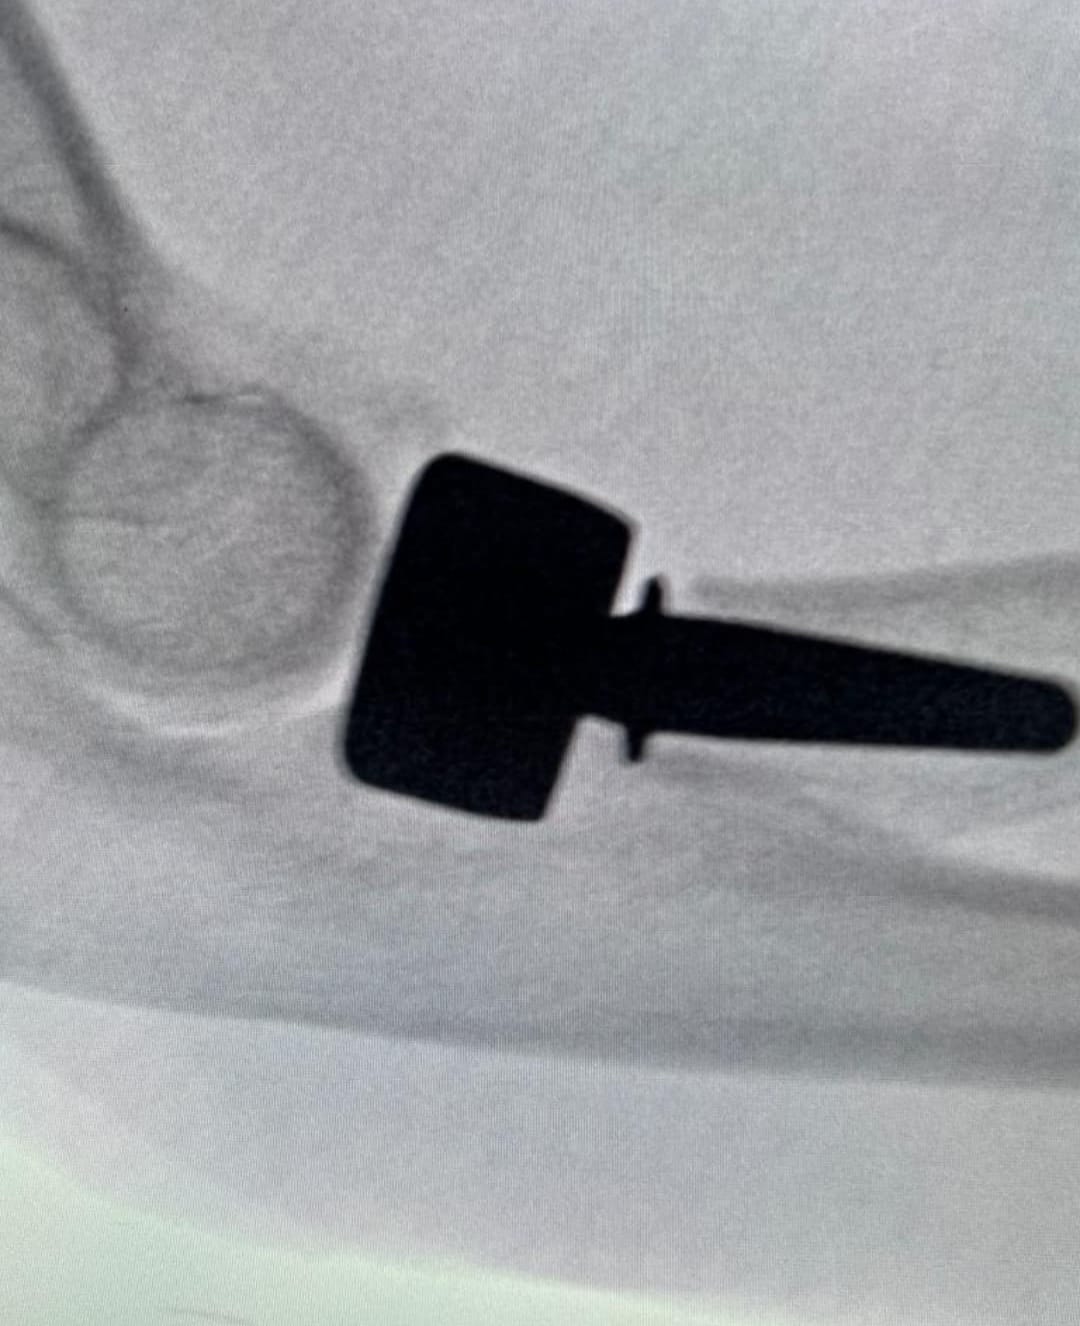

• Cirugía ortopédica reconstructiva

CASOS